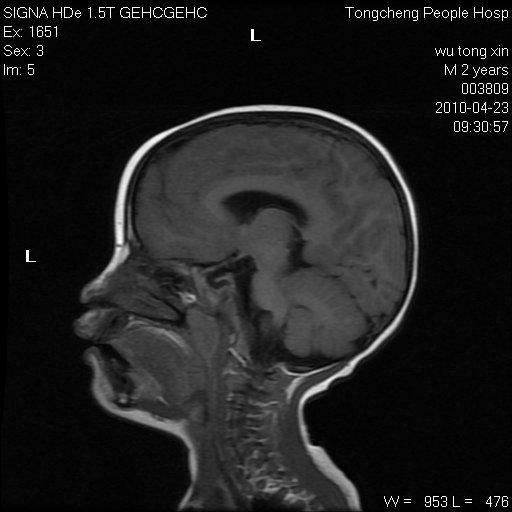

以下是引用赵物学在2010-4-25 12:43:00的发言:[br]巨脑回[br]侧脑室后角低密度影考虑hie或肾上腺脑白质营养不良?[br][br][本贴已被 赵物学 于 2010-4-25 12:51:28 修改过]

以下是引用gaoxiao在2010-4-25 16:54:00的发言:[br]巨脑回畸形。脑白质髓鞘化不良

以下是引用pujunzhi在2010-4-25 21:35:00的发言:[br]考虑 1双侧大脑皮质发育不良 2轻度脑积水 3双侧脑室后角旁片状长t1长t2信号,需继续观察,因为正常小儿此处脑白质的髓鞘化时间可以延迟到4-6岁,才显示正常。